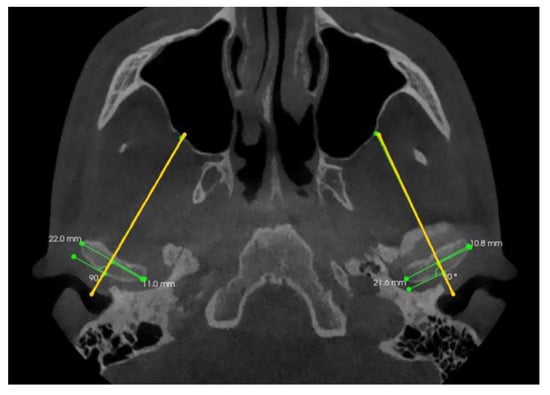

2. Materials and Methods